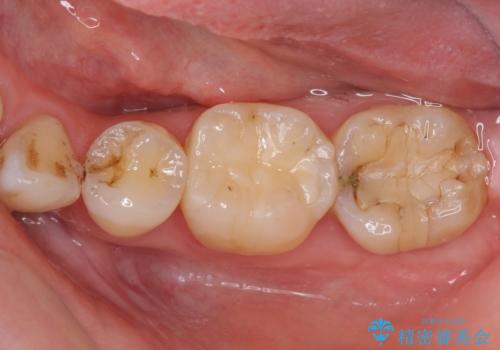

- 下の奥歯に虫歯ができてしまったとのことで来院された患者様です。

他にも気になる歯はありましたが、急を要する1歯のみをセラミックインレーにて修復治療を行うこととしました。

奥歯において、隣の歯と接触する部分に虫歯が及んでしまった場合、その場で充填を行う処置(コンポジットレジン修復)ですと、充填の縁に大きなギャップが生じてしまう可能性が高く、2次的な虫歯を引き起こすことになります。

また、処置した歯の後方にある歯は保険診療で使用するレジンインレーが装着されていますが、縁に虫歯が出来はじめていることが分かります。